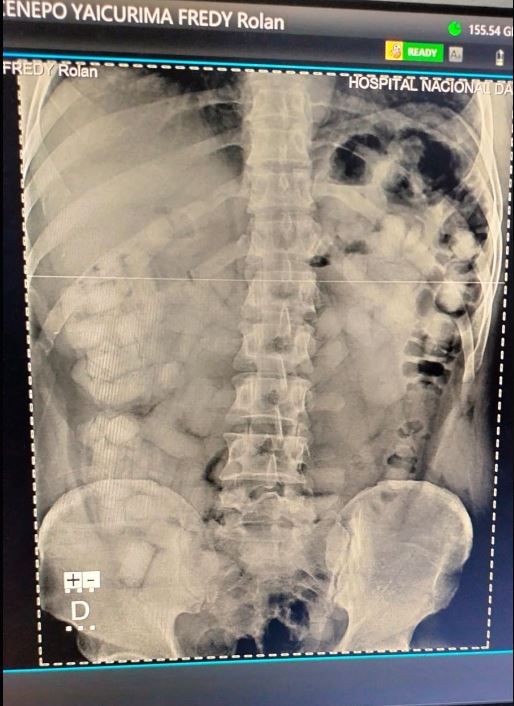

El detenido, identificado como Fredy Rolan Cenepo Yaicurima, de 41 años, presentaba cuerpos extraños en la cavidad abdominal, detectados mediante un examen no invasivo con el Body Scan. Esta sospecha fue confirmada con una radiografía realizada en el hospital Daniel Alcides Carrión. Además de la droga en su interior, a Cenepo Yaicurima se le incautaron 700 euros y un celular, evidencias que apuntan a sus intenciones delictivas.